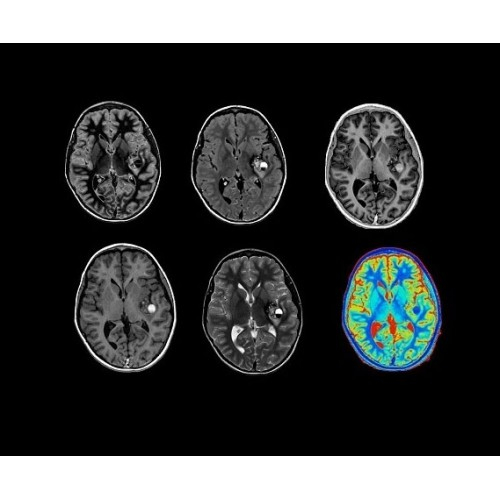

SIGNA Architect 3.0T — это новейший МРТ аппарат компании GE, который предлагает высочайший уровень производительности — в системе 128 приемных каналов, 48 канальная катушка головы, полный спектр клинических возможностей. Высокий уровень комфорта пациента обеспечивают такие особенности как отсоединяемый стол, положение пациента «ногами вперед» для всех видов исследований, SilentWorks — бесшумное и MAGIC — быстрое сканирование.

Теперь возможности МРТ поражают еще больше благодаря ультрасовременным решениям для визуализации с SIGNA Architect 3.0 Тл, объединяющей новейшие достижения в области МР-технологий и интуитивно понятный интерфейс. Система SIGNA Architect, разработанная на базе новой платформы SIGNA Works, представляет собой гармоничное сочетание дизайна и функциональности. Каждый элемент системы направлен на повышение производительности, эффективности клинической практики, финансовых показателей, а также комфорта и безопасности пациента.

Стандартный пакет приложений SIGNA Works позволит вам достичь желаемых результатов в клинической практике благодаря набору высокоэффективных средств визуализации. Программные приложения, входящие в состав данных клинических пакетов, включают широкий спектр контрастов, функции обработки 2D- и 3D-данных, а также возможность коррекции артефактов движения. SIGNA Works предоставляет набор инструментов, необходимых для проведения эффективного клинического исследования.

• NeuroWorks — универсальное решение для визуализации анатомии головного мозга, позвоночника, сосудов и периферических нервов с четкой дифференциацией тканей.

• ImageWorks — повысит производительность МРТ благодаря визуализации высокого качества с MAGIC, четкими результатами пост-процессинга с READYView.